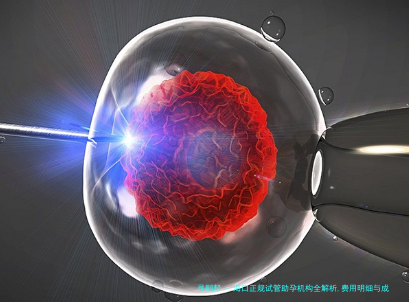

生命的微光:当科技与希望共舞

在椰风轻抚的海口,越来越多的家庭正借助人类辅助生殖技术点亮生育愿望。跟着胚胎基因筛查的精准化、AI评估系统的迭代,试管助孕已从单纯医药学操作演变为交融遗传学、心理学与个体化服务的生命工程。怎么样在技术红利与隐藏风险间寻到平衡?怎样为不同群体铺就安全、正当的生育路径?本文将揭开海笔试管助孕的核心图景。

海口主体机构已全方位覆盖胚胎植入前遗传生物学检测技术(PGT),可以筛选查染色体异样及单基因遗传性疾病(如地中海贫血),阻断成功率高达99.5%。部分机构结合动向胚胎监测系统(Time-lapse),通过及时影像改良胚胎筛查,使优质胚胎获得率提升15%-20%,尤其适用于40岁之上高龄或家属遗传病史家庭。

人工智能胚胎评估:人工智能系统可量化剖析胚胎模样、决裂速度等指标,预测着床潜力,将囊胚筛选准确率提高20%。